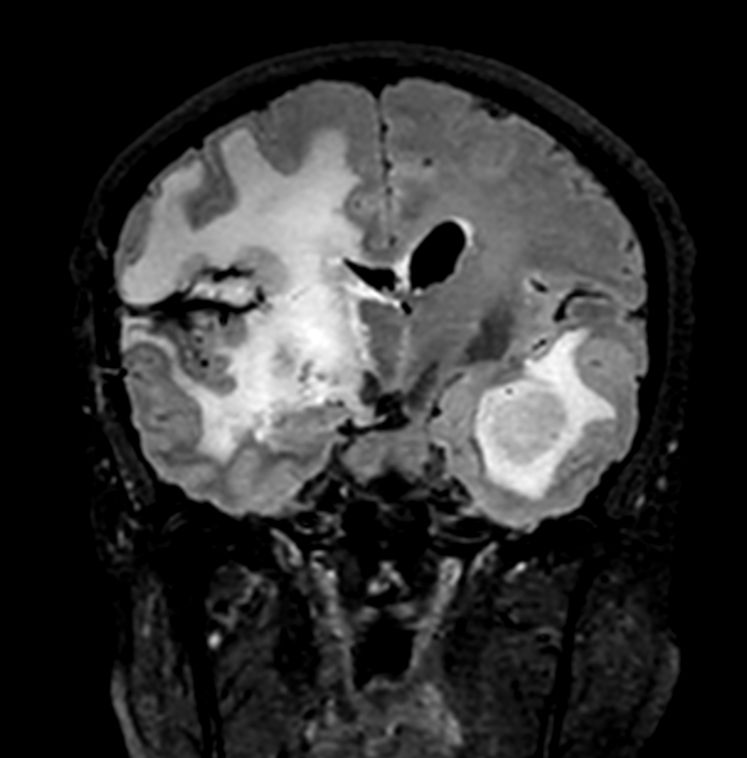

Patient with a large brain lesion. AI based SmartSpeed is utlized to shorten scan time without compromise in image quality. Advanced imaging techniques like pCASL and 3D APT are used to perform contrast-free brain imaging to assess perfusion and tumoral activity. SWIp 3D susceptibility weighted offers the high sensitivity required to visualize deoxygenated (venous) blood or calcium deposits. A single synthetic (SyntAc) brain quantification scan is added. The resulting data of this scan can be used as input for advanced third party processing software* to synthesize MR images with different contrasts, brain parenchyma fraction maps and/or brain segmentation maps.

3D FLAIR (Coronal reformat)